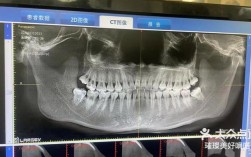

- 必须专业评估: 绝对不要自行决定顺序! 必须同时咨询经验丰富的正畸医生和专业的种植牙医生,他们需要通过详细的临床检查(口内检查、模型分析)、X光片(全景片、头颅侧位片、CBCT)等影像学评估,共同讨论并为你制定个性化的、最优的治疗计划。